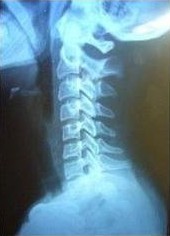

患者饺子今年14岁,平日特别喜欢通过手机、平板看电子书和玩游戏。今年因为新冠的影响,学校迟迟不能入校,所有课程通过网络视频授课,这就更加增加了手机、平板的使用时间。以往在学校时还有课外活动时间,回到家后孩子爸爸还会带着饺子打打羽毛球、篮球,今年这些却都不能做了,饺子在家只能网络上课、看电子书、玩游戏。有一天饺子告诉妈妈,脖子不舒服,还会感觉头晕,这一下妈妈着急了,带着饺子到医院看骨科,拍片子,显示颈椎曲度变直,大夫告诉饺子妈妈,回家养着吧,别总玩手机,不舒服了贴贴膏药,没事多活动活动。可回到家后小饺子还是总说脖子不舒服,头晕,这可怎么办呢?饺子的姥姥听说后,让饺子妈妈带着小饺子到我的门诊来,我和饺子的姥姥也算是老相识了,治了颈椎又治腰和膝盖。

来到门诊后,查体见:颈椎僵直,按压酸痛明显,压颈试验(-),臂丛神经牵拉试验(-)。给与了推拿正骨治疗,建议每周至少2次推拿,并且要结合功能锻炼,颈下垫浴巾卷辅助曲度恢复,因一周只出一次门诊,叮嘱饺子妈妈在我的学生门诊时找他治疗,周一找我治疗,就这样治疗了一个月后,症状消失了,拍片子,颈椎曲度也恢复了挺多。